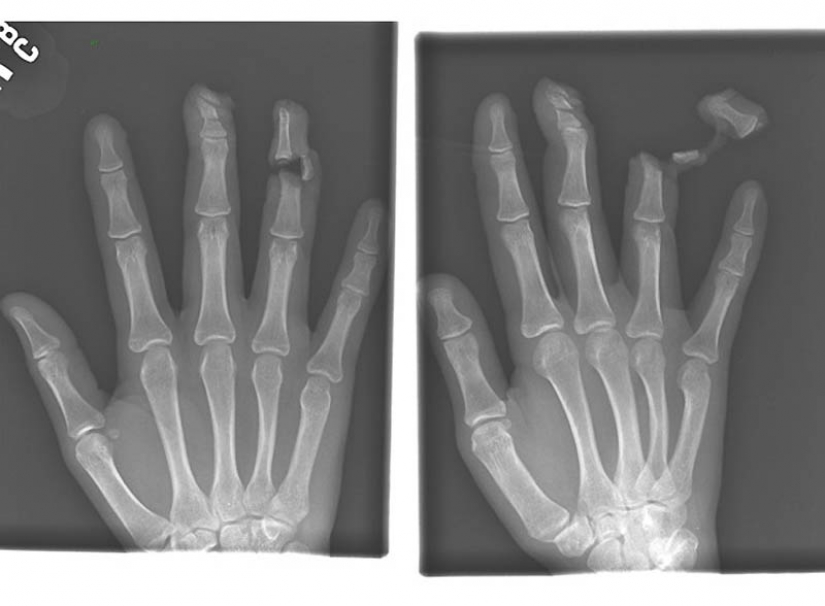

4. The nail in the bones of the index and middle fingers of adult men.